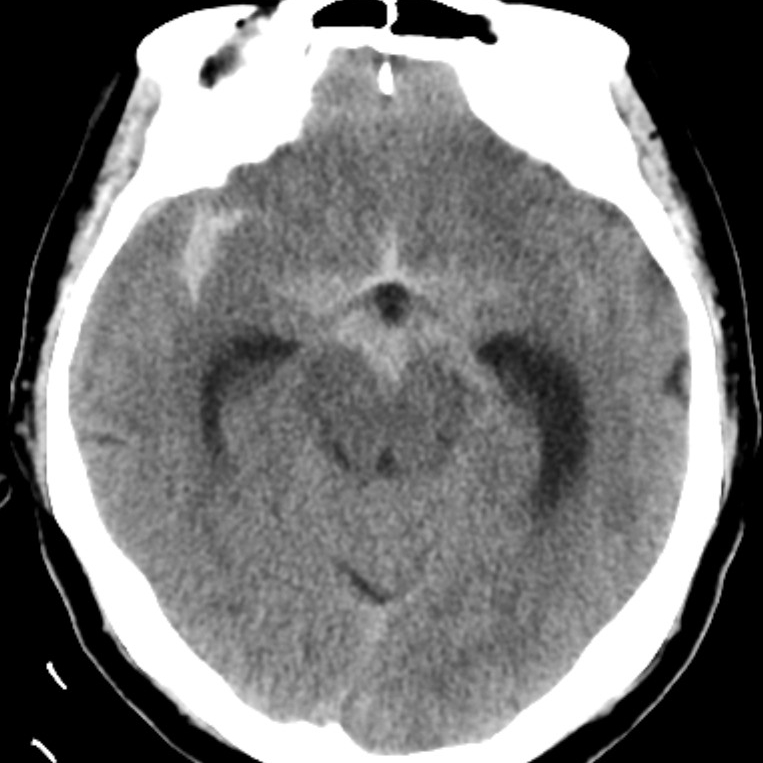

病例一为77岁女性患者,既往高血压病史。因“突发剧烈头痛伴恶心2天”前来清华大学附属垂杨柳医院急诊科就诊。头颅CT检查提示蛛网膜下腔出血,头颈动脉CTA提示右侧大脑中动脉M1段分叉处宽颈动脉瘤。神经外科脑血管病介入团队急诊为患者实施了全脑血管造影术(DSA),造影显示动脉瘤不规则,可见子囊,宽颈,主要累及下干。团队采取了支架辅助弹簧圈栓塞术,患者颅内“不定时炸弹”被成功拆除。动脉瘤达到致密栓塞,载瘤动脉通畅。住院半个月后顺利出院,无神经功能障碍。

▲头颅CT显示蛛网膜下腔出血

病例二为58岁女性患者。因“突发剧烈头痛伴呕吐3小时”就诊于清华大学附属垂杨柳医院急诊科,行头颅CT检查提示蛛网膜下腔出血。患者嗜睡,频繁呕吐,不排除颅内再出血。为争分夺秒抢救患者生命,神经外科脑血管病介入团队紧急为患者实施了DSA,显示左侧大脑中动脉分叉处宽颈动脉瘤,主要累及下干。术中采取双微导管技术,于动脉瘤内填塞弹簧圈,并置入一枚支架保证致密栓塞和下干分支血管的通畅。成功“拆弹”,化险为夷,患者恢复过程顺利,出院时无神经功能缺损。